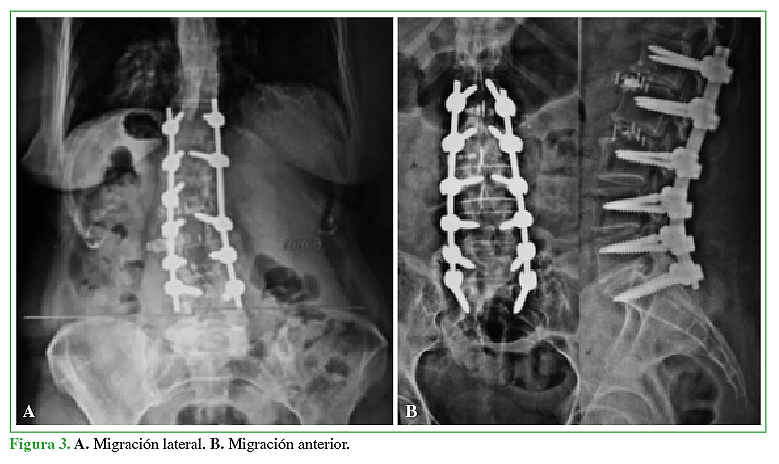

Complicaciones tempranas en los primeros 50 casos de cirugía mínimamente invasiva lateral a la columna lumbar

Acceso mediante suscripción PDF Acceso mediante suscripción PDF_EN (English) Acceso mediante suscripción Figura 1 Acceso mediante suscripción Figura 2 Acceso mediante suscripción Figura 3 Acceso mediante suscripción Tabla 1 Acceso mediante suscripción Tabla 2 Acceso mediante suscripción Tabla 3 Acceso mediante suscripción Tabla 4 Acceso mediante suscripción Tabla 5 Acceso mediante suscripción HTML -